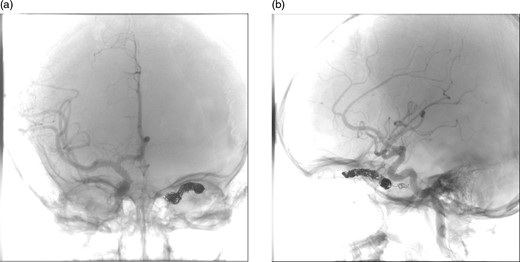

(a) and (b) Post-procedural digital subtraction angiogram under general anaesthesia shows no evidence of a residual CCF following coil embolization.

The patient was discharged 3 days later and a follow-up brain magnetic resonance imaging (MRI) was conducted 4 months afterward, which showed some residual proptosis. The superior ophthalmic vein was prominent but clearly less prominent than previous imaging. On a routine outpatient follow-up, her proptosis had significantly improved with reduction of the corneal injection, she reported no headaches and normal vision. A follow-up IR cerebral angiogram was conducted 4 months later that revealed no evidence of a residual CCF.